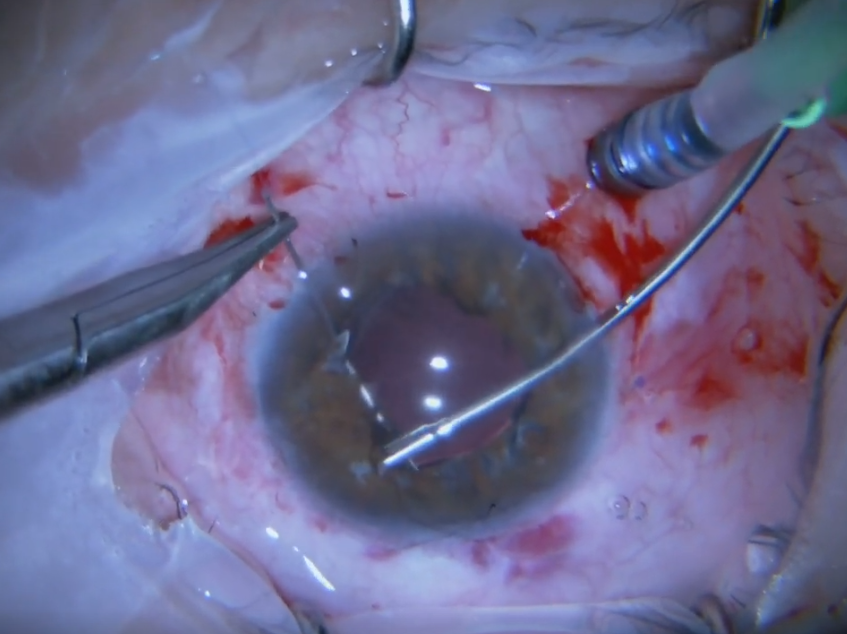

2026 Nisan Ayın Videosu

Travmatik Tek Taraflı İOL Dislokasyonunda Sağlam Skleral Fiksasyonun Korunması i ...

Devamı